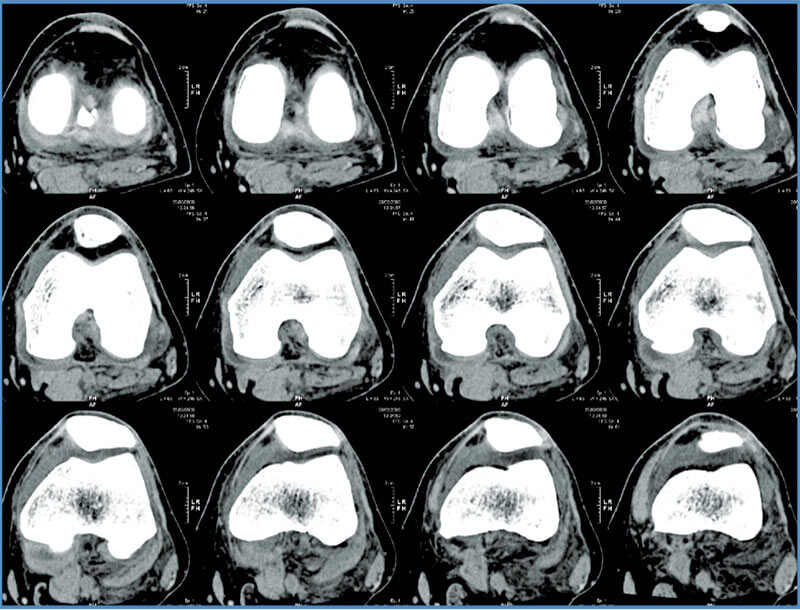

Mako Robotic-Arm Assisted Technology provides you with a personalized surgical plan based on your unique anatomy. First, a computerized tomography (CT) scan of the diseased hip or knee joint is taken. This CT scan is uploaded into the Mako System software, where a 3D model of your hip or knee is created. This 3D model is used to pre-plan and assist your surgeon in performing your joint replacement procedure.